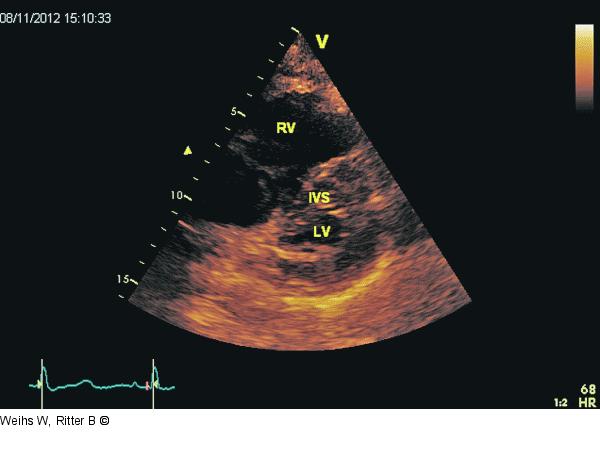

Abbildung 3: Septum Parasternaler Querschnitt. Diastolische und systolische Abplattung des Septums als Hinweis auf eine rechtsventrikuläre Druckbelastung („D-Sign“). RV: rechter Ventrikel; LV: linker Ventrikel; IVS: intraventrikuläres Septum. |